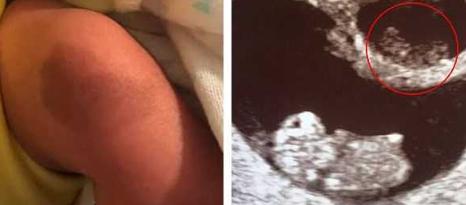

据《每日邮报》2月11日的报道,美国女子基斯利沃尼亚·吉文斯在今年初产下的儿子腿部,有一个特殊的印记,非常像她在怀孕时候他的双胞胎姐姐的B超影像,原来这名妈妈怀的是龙凤胎,姐姐胎死腹中被弟弟吸收了。

没想到肚子里存活的这个胎儿健康的生出来了,是个男宝宝,并且腿上的膝盖处有一个形状很特殊的胎记,吉文斯发现这个胎记很像之前另一个胎儿的B超影像,也就是陪伴了他好几周最后被他吸收的姐姐。

吉文斯感到非常惊讶,这应该是未出生的姐姐给弟弟留下的特殊回忆。